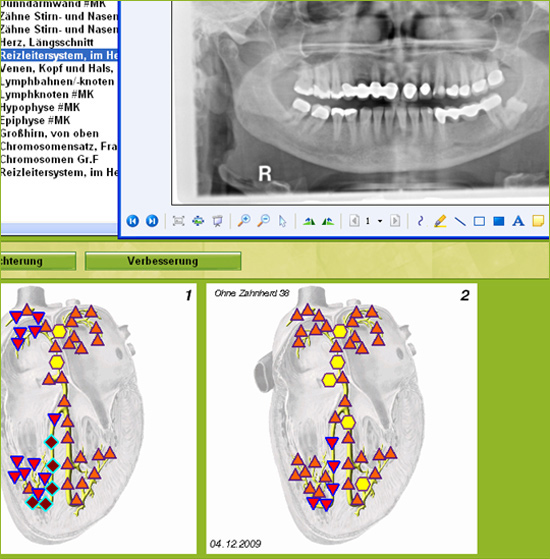

Test of X-ray image

Test after treatment